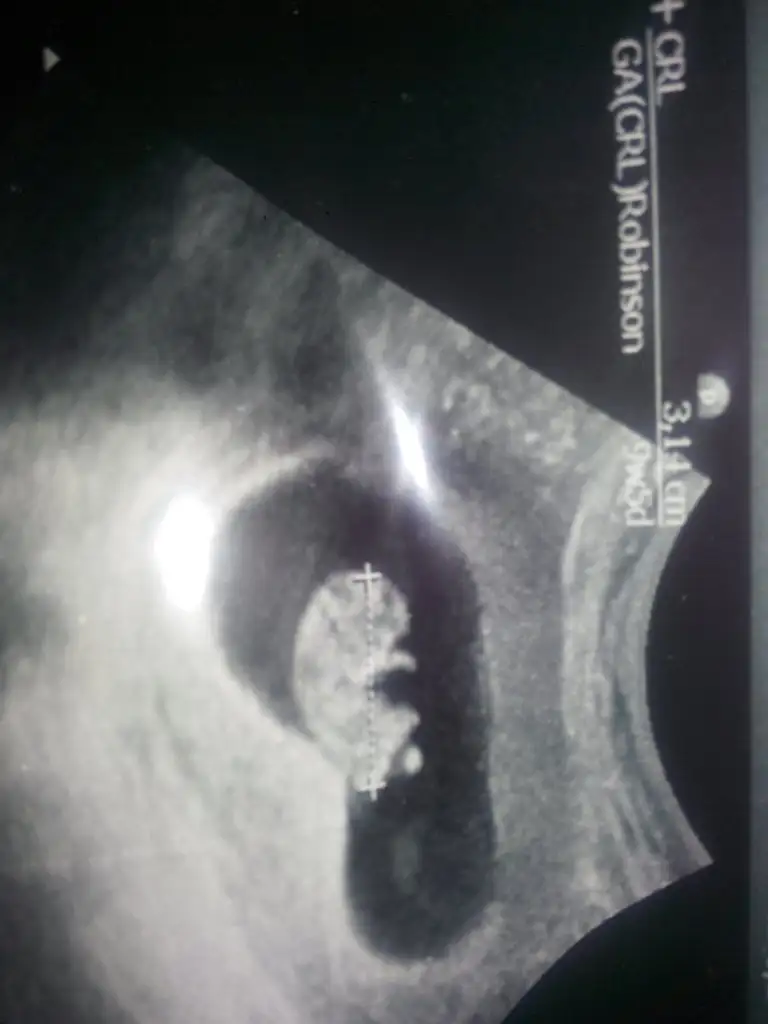

Teyzesi kollarini oynatiyodu hareket de gorduk cok sukur